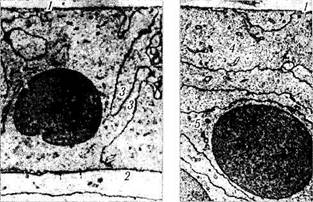

Центральная зона. Центральная зона состоит из относительно постоянного количества клеток, число которых медленно уменьшается с возрастом [22, 23, 798]. Эпителиоциты полигональной формы (рис. 3.4.9, 3.4.10, а), ширина их — 11 —17 мкм, а высота — 5—8 мкм. Своей апикальной поверхностью они прилежат к наиболее поверхностно расположенным хрустали-ковым волокнам. Ядра смещены к апикальной

Рис. 3.4.10. Ультраструктурная организация эпителиальных клеток капсулы хрусталика промежуточной зоны (а) и экваториальной области (б) (по Hogan et al., 1971):

1 — капсула хрусталика; 2 — апикальная поверхность соседней эпителиальной клетки; 3 —пальцевые вдавления в цитоплазму эпителиальной клетки соседних клеток; 4 — эпителиальная клетка, ориентированная параллельно капсуле; 5 — ядросодер-жащая эпителиальная клетка, расположенная в коре хрусталика

поверхности клеток большого размера и имеют многочисленные ядерные поры. В них, как правило, два ядрышка.

Цитоплазма эпителиоцитов содержит умеренное количество рибосом, полисом, гладкий и шероховатый эндоплазматический ретикулум, маленькие митохондрии, лизосомы и гранулы гликогена. Выражен аппарат Гольджи. Видны цилиндрической формы микротрубочки диаметром 24 нм, микрофиламенты промежуточного типа (10 нм), филаменты альфа-актинина [798].

Цитоплазма эпителиоцитов содержит малочисленные органоиды [201]. Имеются короткие профили шероховатого эндоплазматическо-го ретикулума, рибосомы, маленькие митохондрии и аппарат Гольджи [13] (рис. 3.4.10, б). Количество органоидов нарастает в экваториальной области по мере увеличения количества структурных элементов цитоскелета [863] актина, виментина, белка микротрубочек, спект-рина, альфа-актинина и миозина. Существует возможность различить целые актиновые сете-подобные структуры, особенно видимые в апикальной и базальной частях клеток [865, 866, 1209]. Помимо актина в цитоплазме эпителиальных клеток выявлены виментин и тубулин [531]. Предполагают, что сократительные мик-рофиламенты цитоплазмы эпителиальных клеток способствуют путем их сокращения перемещению межклеточной жидкости.